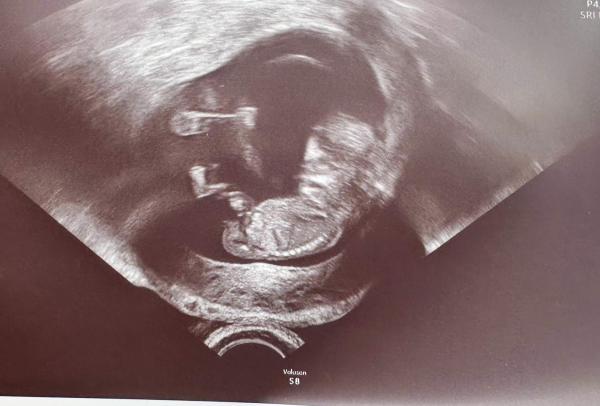

Hallo bin in der 12 ssw und würd mich mal interessieren was ihr denkt ? Laut der NUB Theorie. Lg

Bild zu NUB ? - Schwanger - wer noch? Rund um die Schwangerschaft

Hi Ich tippe vorsichtig auf Team blau Lg